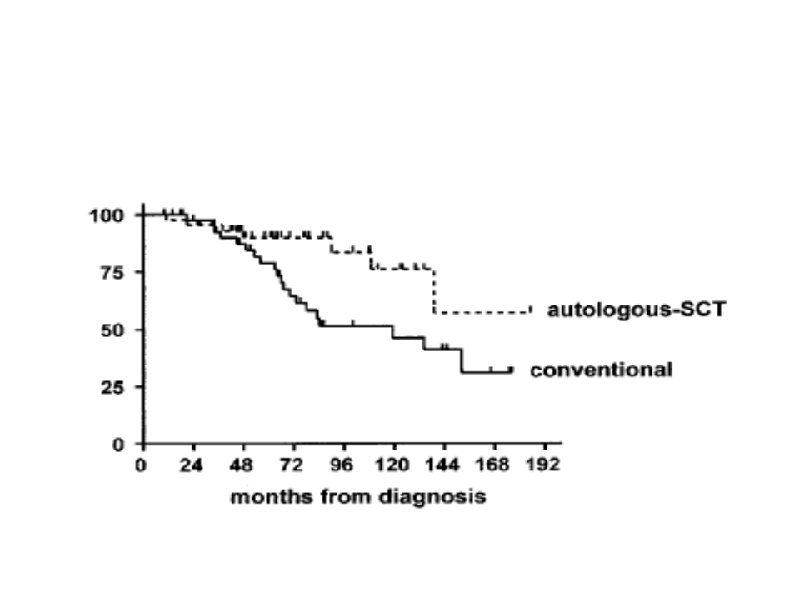

Тактика лечения больных ХЛЛ на постремиссионном этапе